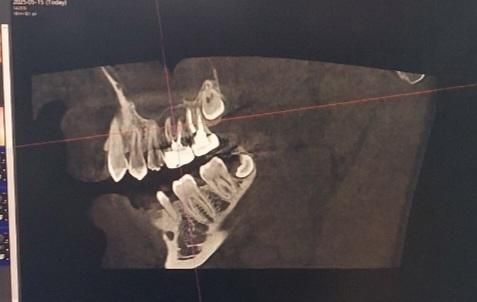

Ct촬영 영상입니다. 첫번째 사진의 경우, 윗니중에 오른쪽에서 3번째 치아가 문제가 되는 금니입니다. 해당 금니의 주변잇몸이 거의 녹아서 상악동과 염증이 연결된 형태라고 합니다. 또한 해당 치아의 뿌리는 총 3개인데 이 중 2개의 뿌리주변에 있는 잇몸은 거의다 녹았고, 나머지 1개의 뿌리 주변의 잇몸도 많이 녹았다고합니다. 이정도면은 재신경치료로 최대한 자연치아를 살리는 치료가 의미가 없으려나요..ct사진으로 정확히 판독해주시면 감사하겟습니다!

• 1번 째 사진

CT 영상은 여러각도와 분할로 봐야하기에 상기 이미지로는 한계가 있으나 이미 동요도가 어느정도 있는 상태라면 재신경치료로도 살리기 힘든 치아로 보임니다. 통증을 통반한 상태이면 활성화 상태이므로 발치가 적응증일거로 생각됩니다. 골소실이 더 진행되면 발치후 치유도 오래걸리는걸 감안하면 추후 임플란트를 고려중이시라면 빠른 결정이 나을것으로 생각됩니다.

현재 상태에서는 재신경치료를 하더라도 살릴 가능성은 매우 적습니다. 이미 상당 부분의 치조골이 소실되어 있는 상태입니다. 시간을 더 지체하게 될 경우에는 상악동까지 염증이 파급되거나 치조골이 더 많이 소실될 수 있으므로 늦지 않게 발치하는 것이 필요해보입니다.

사진으로 봤을 경우에는 치아 뿌리 쪽에 큰 병소가 보입니다. 신경관 내부가 오랫동안 감염이 되어 있거나 치아뿌리에 금이 갔을 경우 사진처럼 염증이 커질 수 있습니다. 취업 분위기 금이 같다면 치아를 발치해야 할 수도 있기 때문에 정확한 확인을 위해서 치과에서 진료를 받아보는 것이 좋습니다.

만성 염증으로 인해 치아 뿌리 주변 잇몸뼈가 녹아있는 상태가 맞습니다. 이미 신경치료를 한번 한 상태인데 호전되지 않는 경우, 더 악화되는 경우 재신경치료의 성공률은 낮습니다.